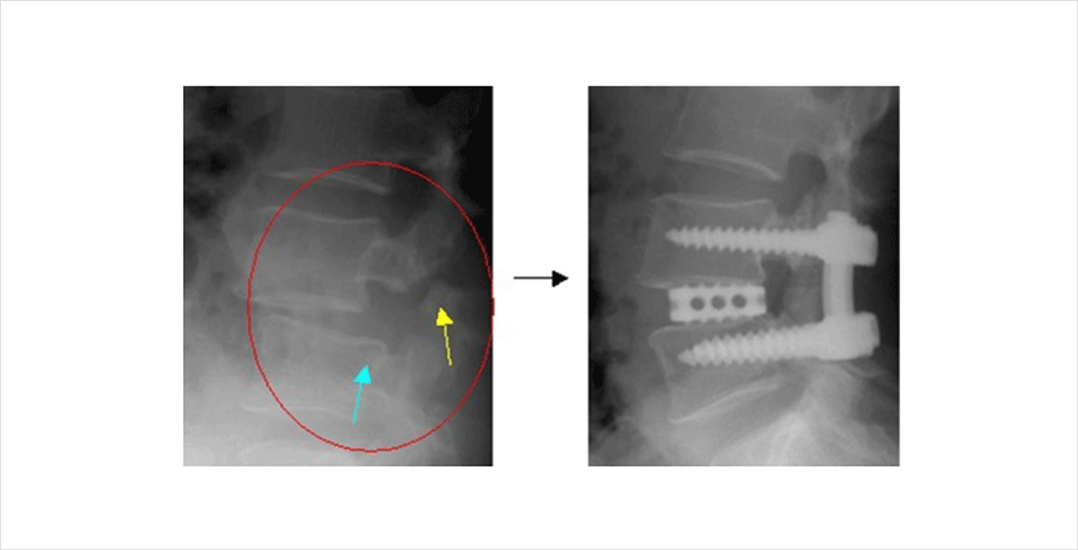

척추 뼈의 구조를 볼 수 있으며 척추관절과 관절 사이의 분리, 척추뼈의 밀려난 정도를 확인, 진단에 도움이 됩니다. 또한 척추의 퇴행성 변화로가시뼈, 관절의 비대등을 볼 수 있습니다. 단순 방사선 검사 중 굴곡, 신전 검사는 척추뼈의 밀려나는 정도의 변화로 척추 불안정 상태가 있는지를 알 수 있습니다.

척추전방전위증에서 가장 먼저 고려되어야 할 치료는 안정과 보존적 치료입니다. 통상적으로 증상이 있는 척추전방전위증 환자의 10~15% 만이 수술적 치료가 필요하다고 알려져 있습니다. 등급 1,2의 환자는 증상을 고려하여 수술을 결정하는 것이 바람직합니다. 전방 전위가 증가하는 경우는 10% 정도에 불과합니다. 등급 3,4의 환자에서 배변 배뇨 장애를 동반하는 마미총 증후군이 발생한 경우에는, 빠른 시간 안에 신경 감압 수술이 필요합니다.대부분 보존적 치료로 관리가 가능하나 유증상 척추전방전위증의 경우 보존적 치료보다 수술적 치료가 통증의 감소 및 기능적 회복에 우위가 있다는 최근 연구결과(SPORT 코호트 임상 연구)가 있습니다. 따라서, 통증 조절에 어려움이 있는 환자들의 경우, 수술적 치료에 대한 적극적인 고려가 필요합니다.